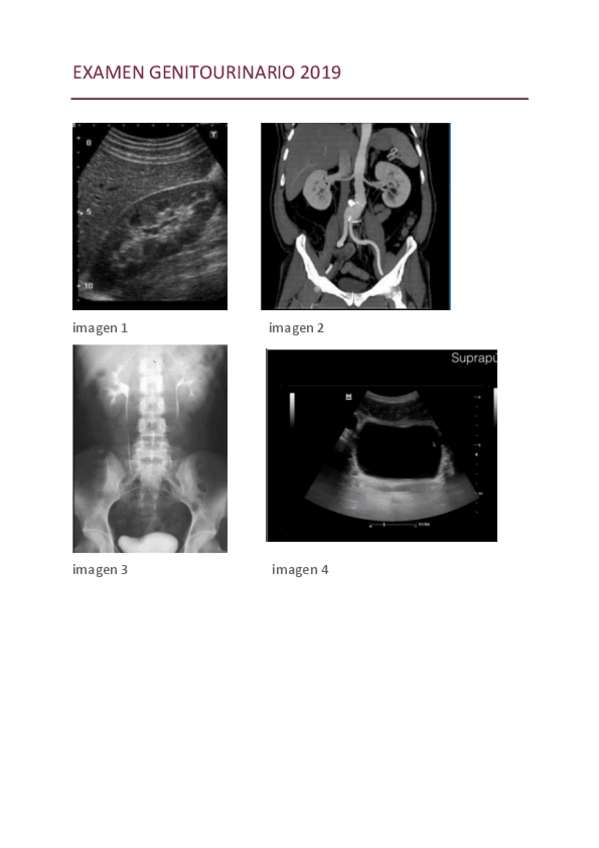

He publicado nuevos examenes de 2º Aparatos Digestivo y Genitourinario: EXAMEN-GENITOURINARIO-2019.pdf

11 páginas